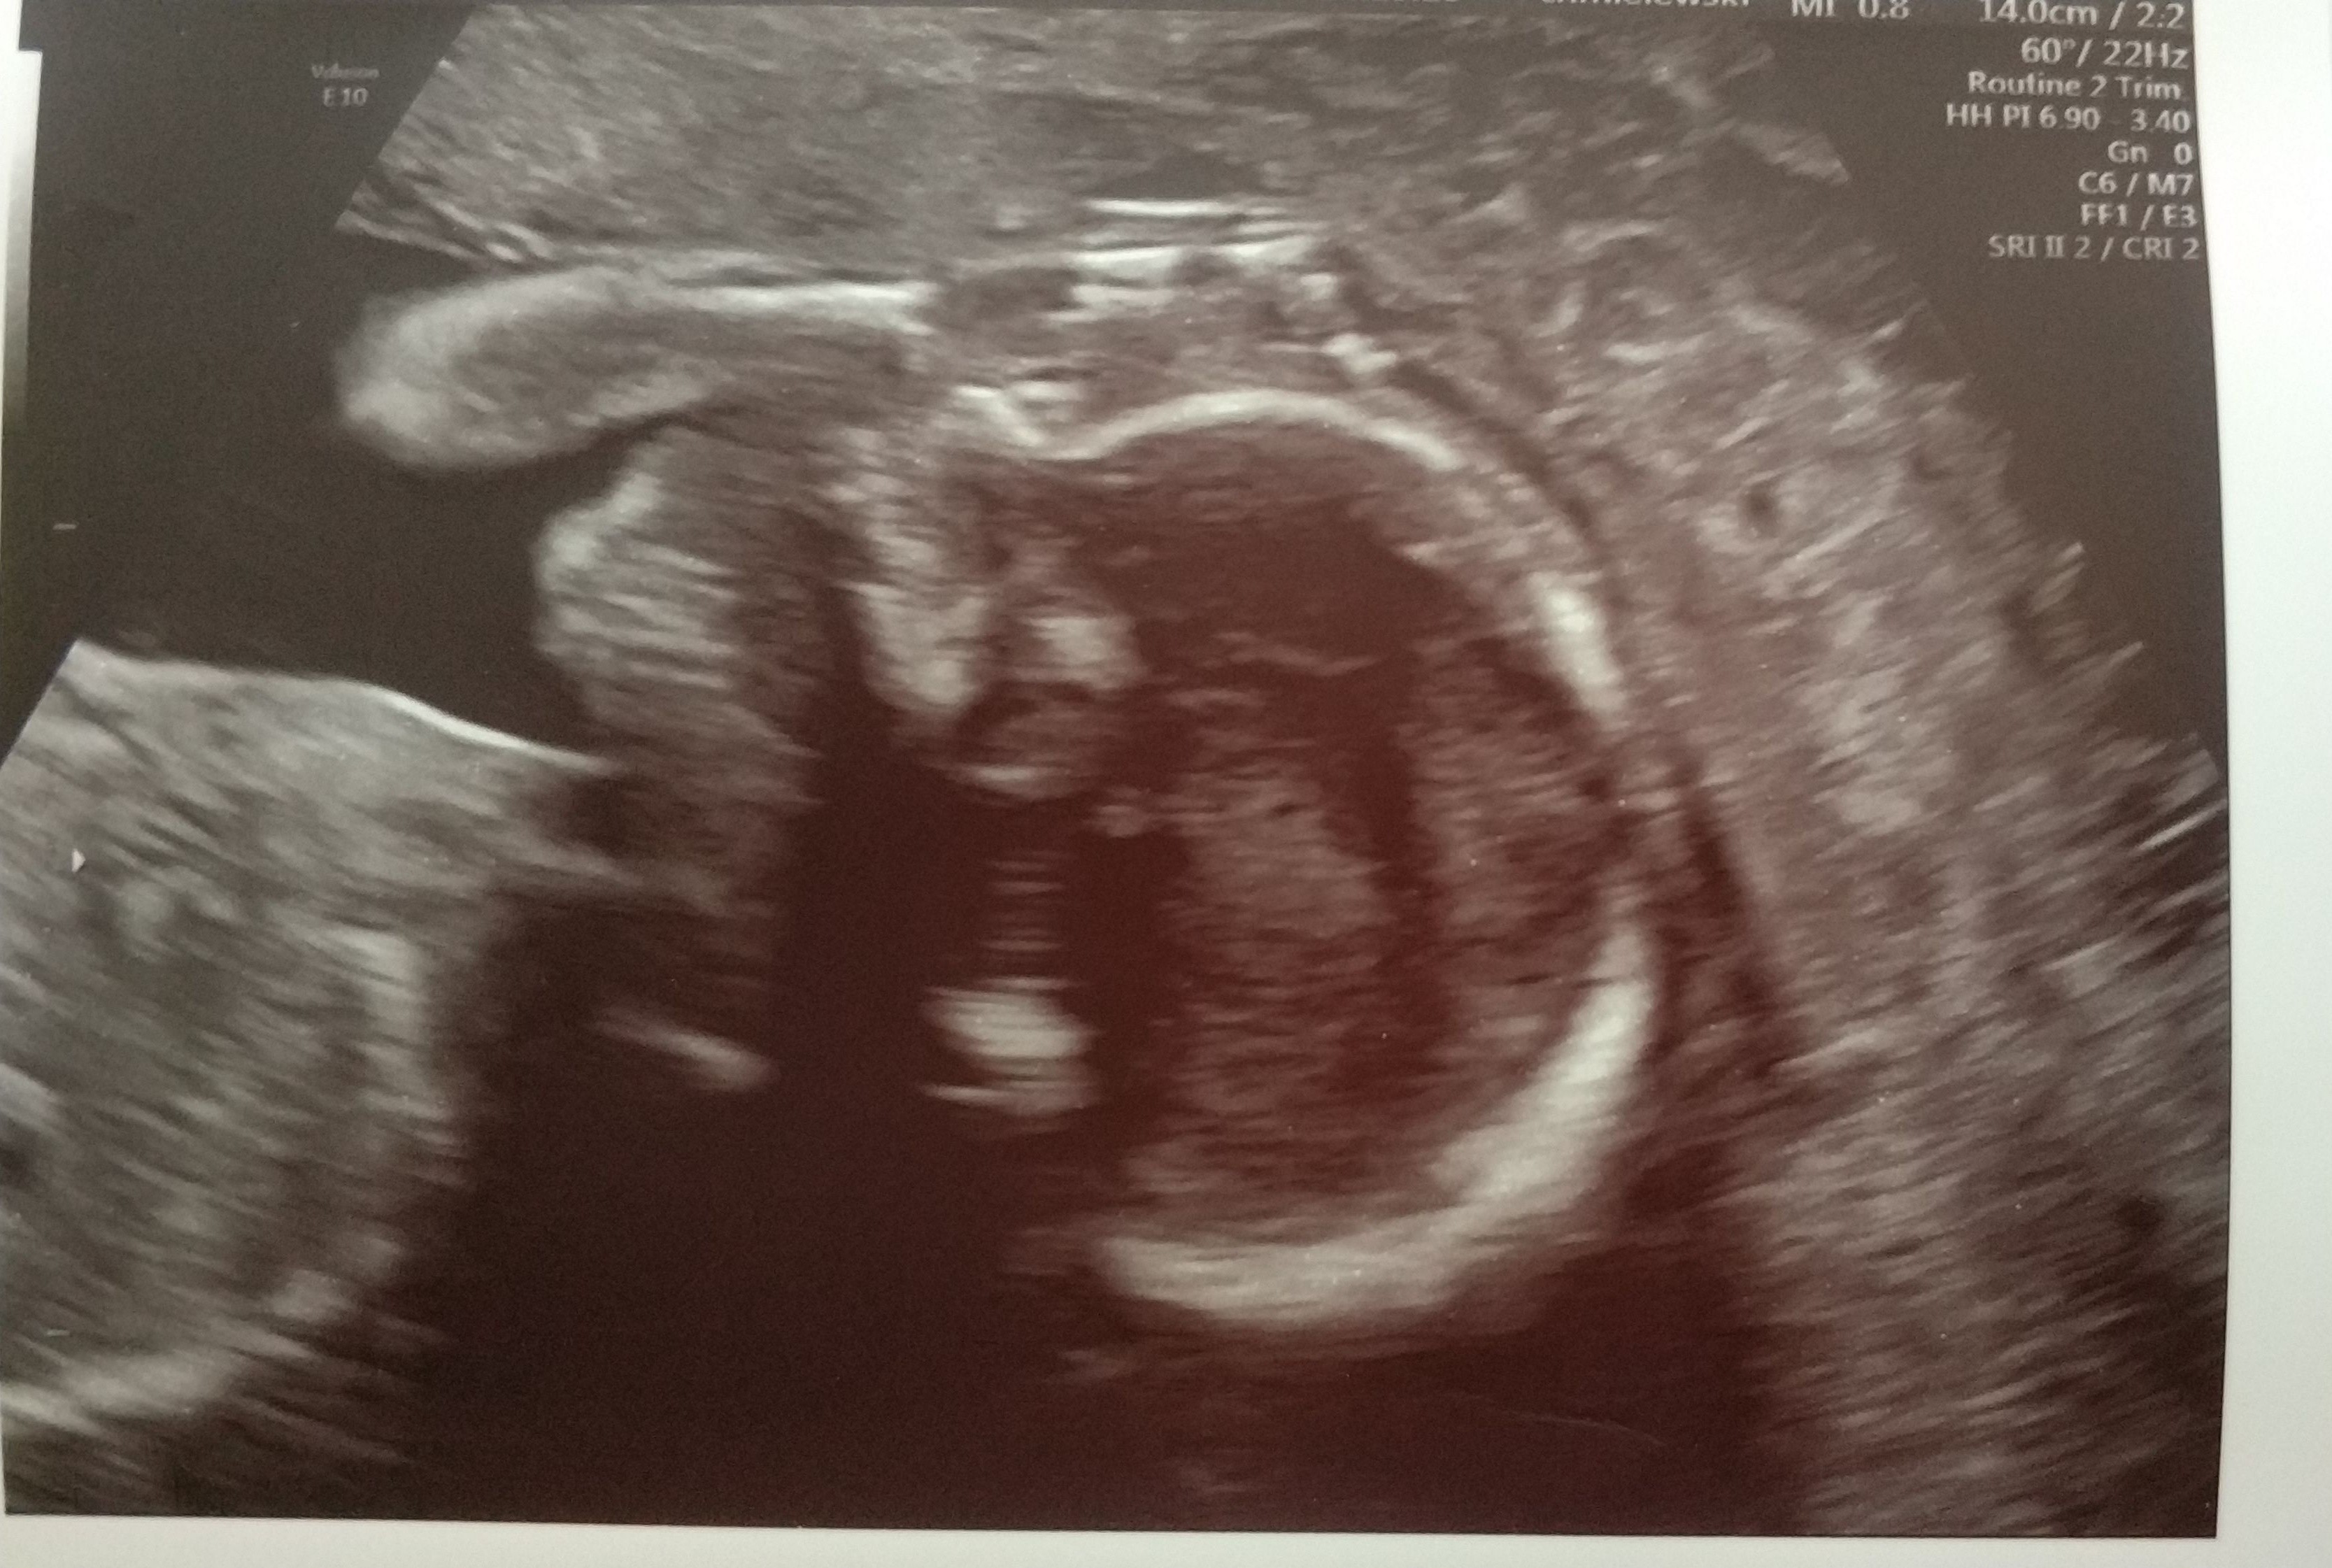

Piekny maluszekMy dzisiaj po badaniach połówkowych. Kajtek, uparty jak mama nie chciał współpracować. Wolał świecić jajkami niż pokazać buzię i oczywiście spał . Po za łożyskiem ułożonym bardzo nisko na przedniej ścianie, wszystko jest w jak najlepszym porządku.